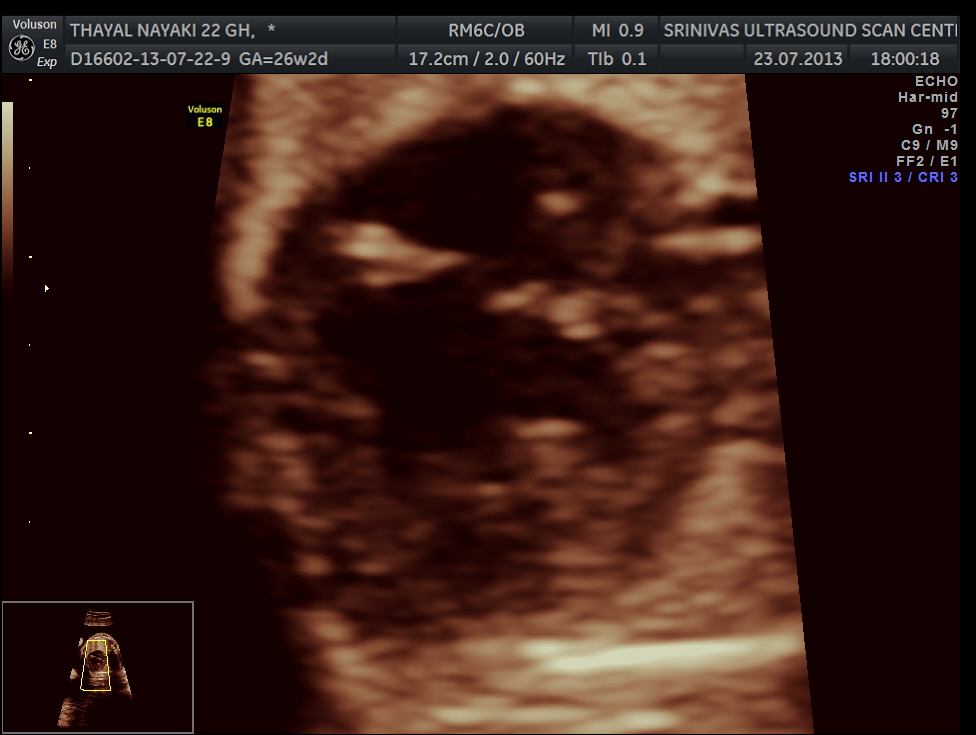

here we can see the pulmonary artery with its two branches arising from the lower (left) ventricle .and the aorta arising from the anterior (right ) ventricle.

pulmonary artery dividing into two